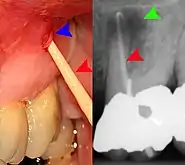

The periodontal ligament becomes inflamed and there may be pain when biting or tapping on the tooth. On an X-ray, bone resorption appears as a radiolucent area around the end of the root, although this does not manifest immediately.[10]: 228 Acute apical periodontitis is characterized by well-localized, spontaneous, persistent, moderate to severe pain.[6]: 125–135 The alveolar process may be tender to palpation over the roots. The tooth may be raised in the socket and feel more prominent than the adjacent teeth.[6]: 125–135

- Radiographs utilized to find dental caries and bone loss laterally or at the apex.

Decay (green) with apical abscess (blue)

Gutta-percha point indicating abscess origin